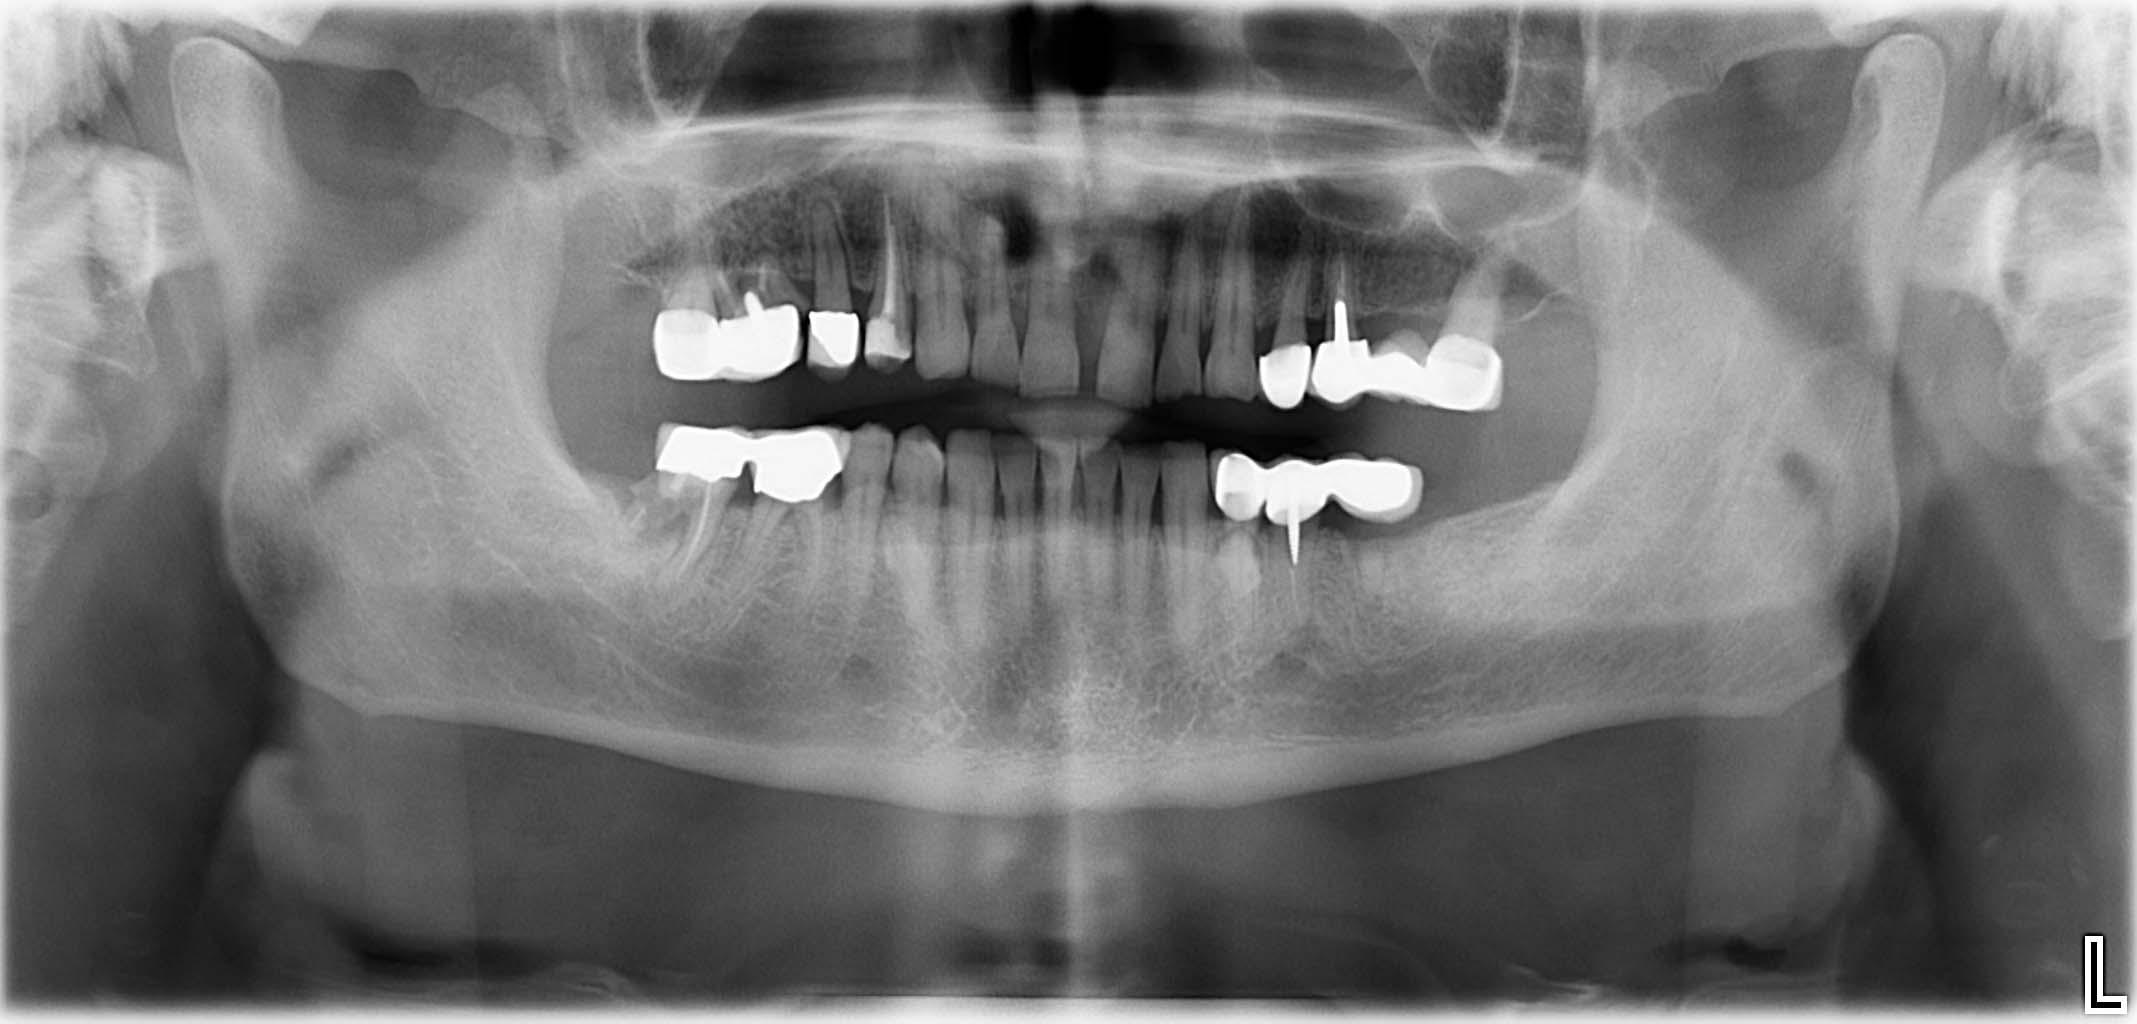

Erfolgreich implantierte Patientenfälle (klinische Fotos)